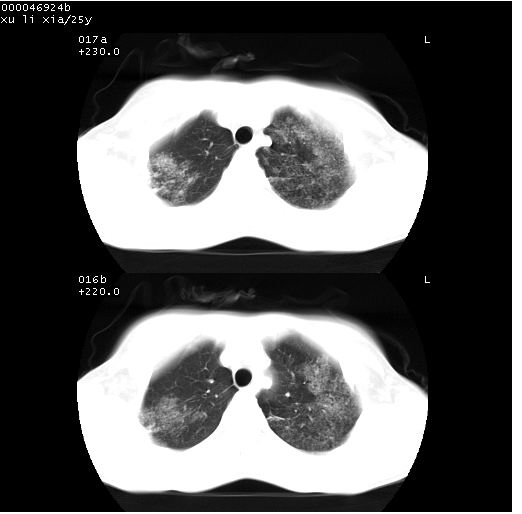

胸部ct轴位平扫(层厚10mm,螺距1.5,重建间隔10mm),图像如下:

病灶呈地图样分布于肺外围,与正常组织分界清晰+弥漫性磨玻璃影中见小叶间隔增厚呈碎石路样表现+年轻女性,无明显临床症状=肺泡蛋白沉积症?

双肺病灶以渗出影搀杂斑点状阴影为主,部分阴影融合成团片,并沿纹理明显见播散灶。支持楼主:两肺感染性病变(结核可能性大)!